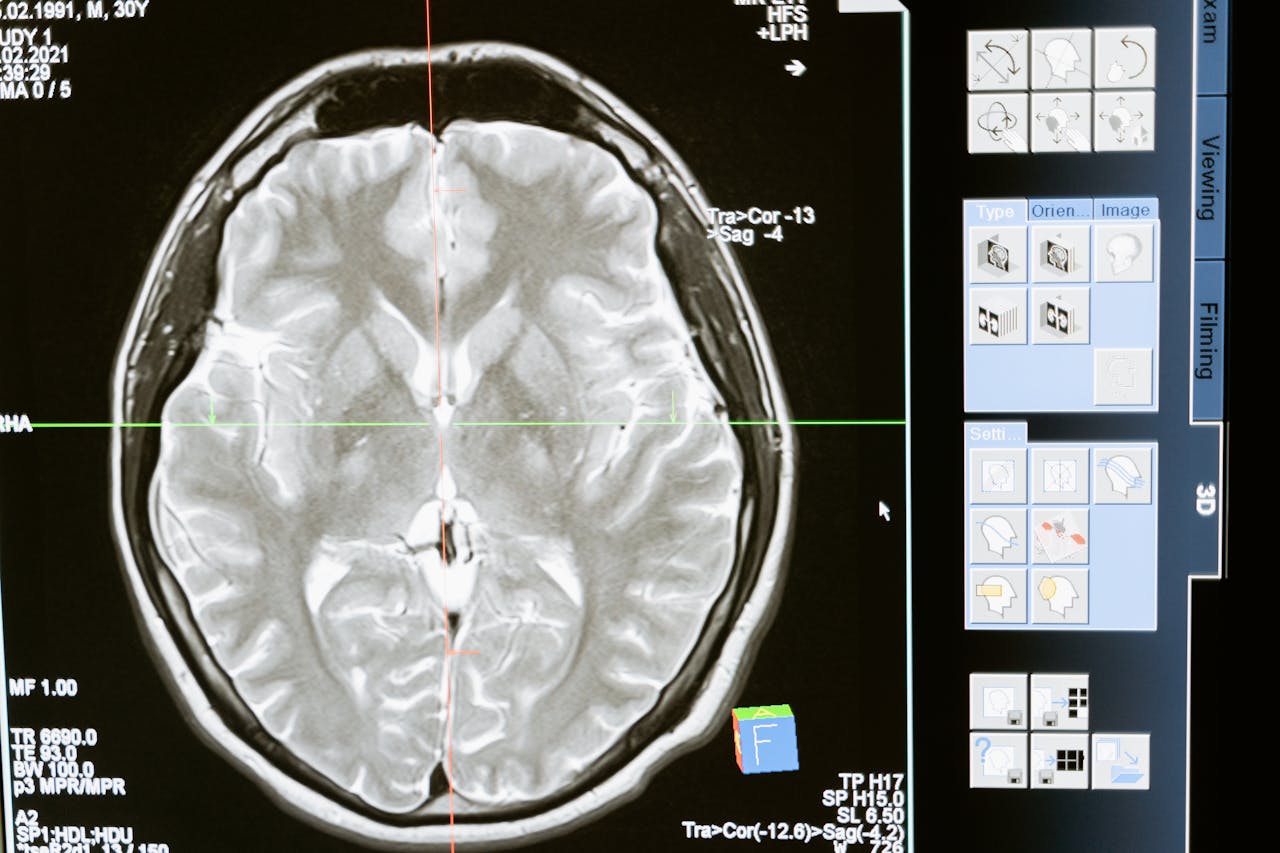

- rezonans magnetyczny przysadki z kontrastem.

photo by MART PRODUCTION/pexels